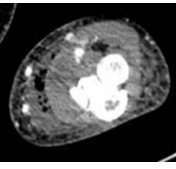

A Rare and Interesting Case of Sciatic Nerve Compression Due to Proximal Femoral Osteochondroma in a Young Adult – A Case Report

Ninad Kishor Honwadkar , Eknath Deosing Pawar , Abhiram T V , Aravind Chanal , Atharva Alaspure